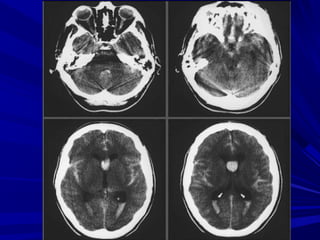

Cắt qua não thất IV

Cắt qua não thất III

Cắt qua thân

não thất bên

Cắt qua trên